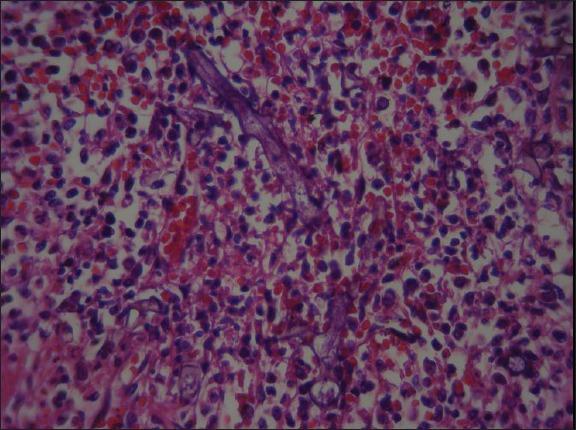

Disseminated mucormycosis is a rare entity most frequently seen in neutropenic patients with hematologic malignancies, post transplants or in patients on deferoxamine therapy. We report a 64-year-old immunocompetent male with an acute pneumonia and a generalized jaundice who died within 24 h. In the autopsy, extensive perforations of spleen and multiple hemorrhage foci on the pancreas were two significant findings. Histopathological study of tissue sections revealed typical zygomycetes hyphae in the left lung, pancreas, spleen and brain. Involvement of pancreas in this patient was one of the rare features of mucormycosis reported occasionally in the literature. Our case implies an unusual clinical presentation of disseminated mucormycosis and highlights that disseminated mucormycosis should be regarded even in the immunocompetent patients.

播散性毛霉菌病是一种罕见疾病,多见于患有血液系统恶性肿瘤的中性粒细胞减少患者、移植后患者或接受去铁胺治疗的患者。我们报告一例64岁免疫功能正常的男性,患有急性肺炎和全身黄疸,在24小时内死亡。尸检时,脾脏广泛穿孔和胰腺多处出血灶是两个重要发现。组织切片的组织病理学研究显示,左肺、胰腺、脾脏和大脑中有典型的接合菌菌丝。该患者胰腺受累是文献中偶尔报道的毛霉菌病罕见特征之一。我们的病例提示播散性毛霉菌病有不寻常的临床表现,并强调即使在免疫功能正常的患者中也应考虑播散性毛霉菌病。